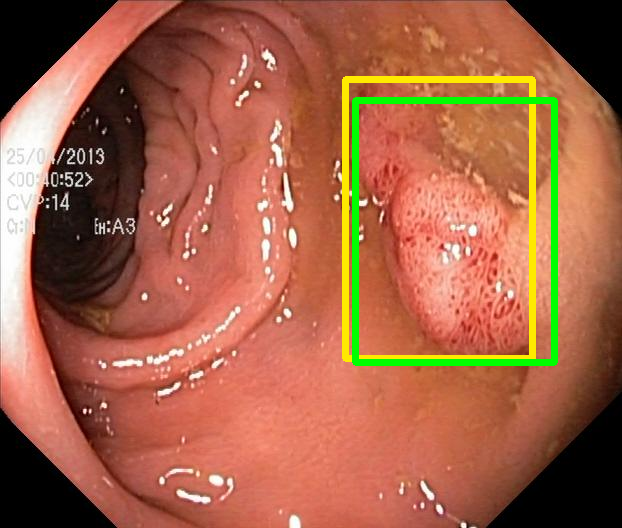

We evaluate the resulting object detection models using the test data, which is pre-processed in the same manner as the validation data, with AP@[.5:.95] (AP for conciseness), AP@.5 (AP50), and AP@.75 (AP75) computed for predicted bounded boxes with a confidence score \geq0.05. For all metrics, a higher value indicates better performance. The results are presented in Table VI, and some examples for predicted bounding boxes with a confidence score \geq0.5 are shown in Fig. 1.

RN-HK-MC RN-HK-BT RN-IN-MC RN-IN-BT RN-IN-SL RN-NA-NA Refer to caption Refer to caption Refer to caption Refer to caption Refer to caption Refer to caption Refer to caption Refer to caption Refer to caption Refer to caption Refer to caption Refer to caption VT-HK-MC VT-HK-MA VT-IN-MC VT-IN-MA VT-IN-SL VT-NA-NA Refer to caption Refer to caption Refer to caption Refer to caption Refer to caption Refer to caption Refer to caption Refer to caption Refer to caption Refer to caption Refer to caption Refer to caption

Figure 1: Targets (yellow bounding boxes) and predictions (green bounding boxes) for two randomly selected instances of the Kvasir-SEG test set. For conciseness, we denote ResNet50s with RN, ViT-Bs with VT, Hyperkvasir-unlabelled with HK, ImageNet-1k with IN, MoCo v3 with MC, Barlow Twins with BT, MAE with MA, supervised pretraining with SL, and no pretraining with NA-NA.